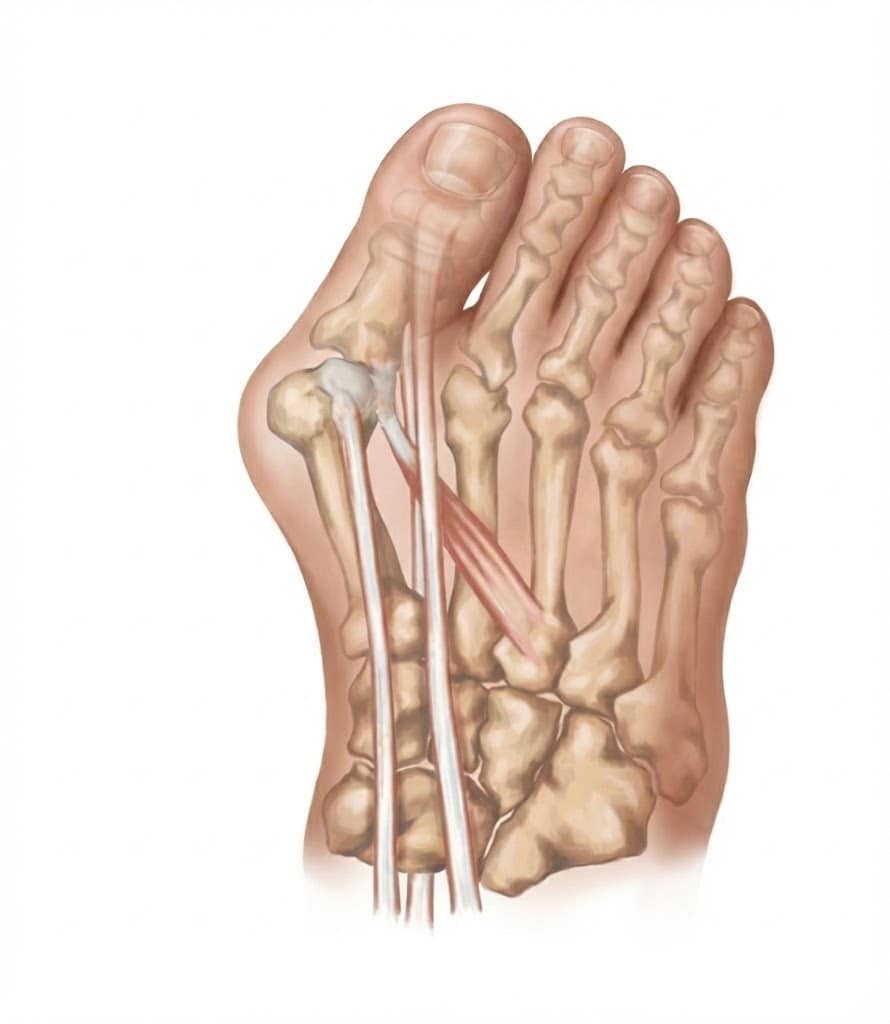

זהו המנגנון שגורם לעיוות להחמיר מעצמו ברגע שהוא מתחיל. הגידים הארוכים המניעים את הבוהן (המיישרים והמכופפים) אמורים לעבור במדויק מעל מרכז המפרק.

- כשהעצמות זזות, הגידים הללו לא מתארכים, אלא נשארים מתוחים בקו ישר (כמו מיתר של קשת).

- כיוון שהעצמות יצרו זווית, הגידים כעת עוברים בצד החיצוני של הזווית (Lateral side).

- בכל פעם שהאדם מכווץ את הבוהן בהליכה, הגידים מושכים את הבוהן עוד יותר חזק הצידה (כמו שמיתר מתוח מכופף את הקשת). זהו מעגל רשע שמחמיר את הזווית בכל צעד.

4. אפקט המיתר (Bowstringing) – שלב האל-חזור

ברגע שציר המפרק נשבר, הגידים הארוכים (EHL ו-FHL) מפסיקים לעבור במרכז המפרק ועוברים לצד הלטרלי (החיצוני).

- וקטור הכוח: כל כיווץ של שריר כדי ליישר או לכופף את הבוהן מייצר כוח וקטורי שדוחף את הבוהן עוד יותר הצידה.

- השריר Adductor Hallucis: שהפך לבלתי מרוסן (כי ה-Abductor Hallucis נחלש וירד לכיוון הסוליה), מושך את הבוהן בחוזקה לכיוון האצבע השנייה.

- זהו השלב בו הטיפול השמרני הופך לפחות יעיל, שכן הכוחות הפנימיים פועלים להחמרת העיוות בכל צעד וצעד.